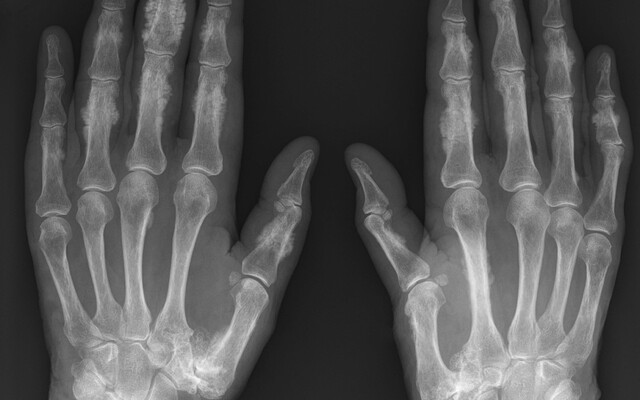

Hier vind je alles op het gebied van ‘Bewegingsapparaat’. Ben jij een orthopedisch chirurg, reumatoloog, sport- of revalidatiearts? Volg dit vakgebied en ontvang een mail wanneer er een nieuw artikel of een nieuwe toets of beeldquiz binnen jouw specialisme is gepubliceerd. Zo ben je altijd op de hoogte.